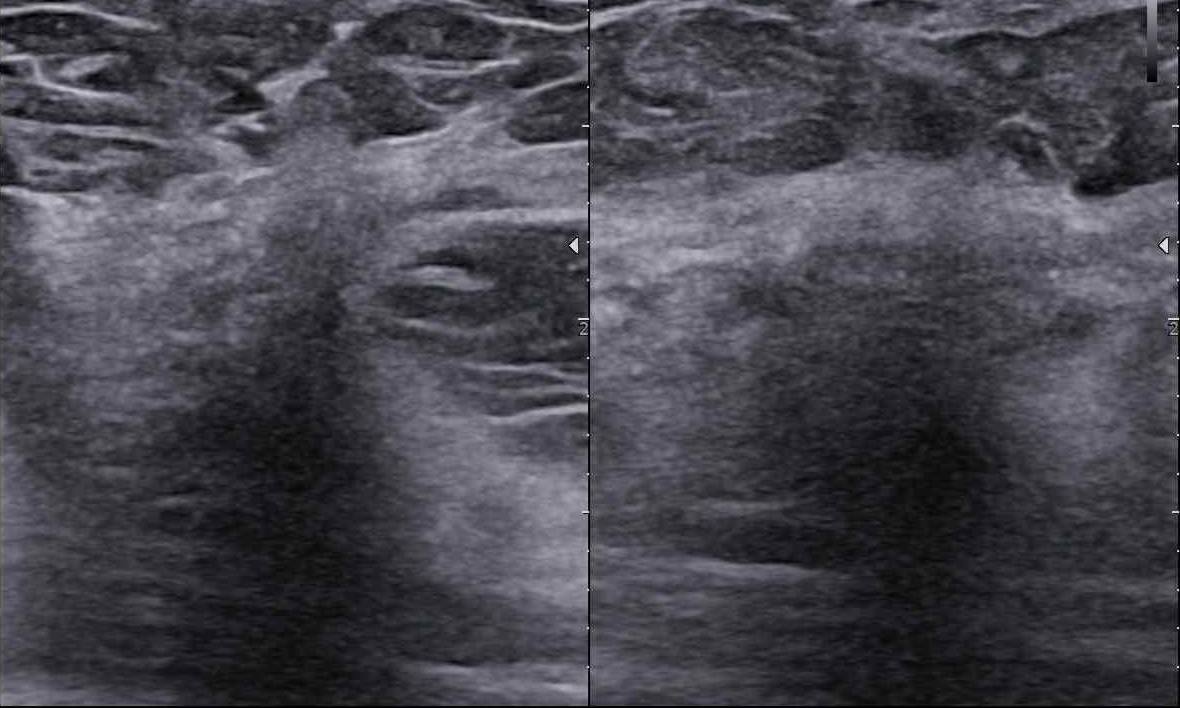

Czy podział BIRADS 4 ma sens? Jak radzić sobie  z BIRADS 4a, b, c?

USG Webinar